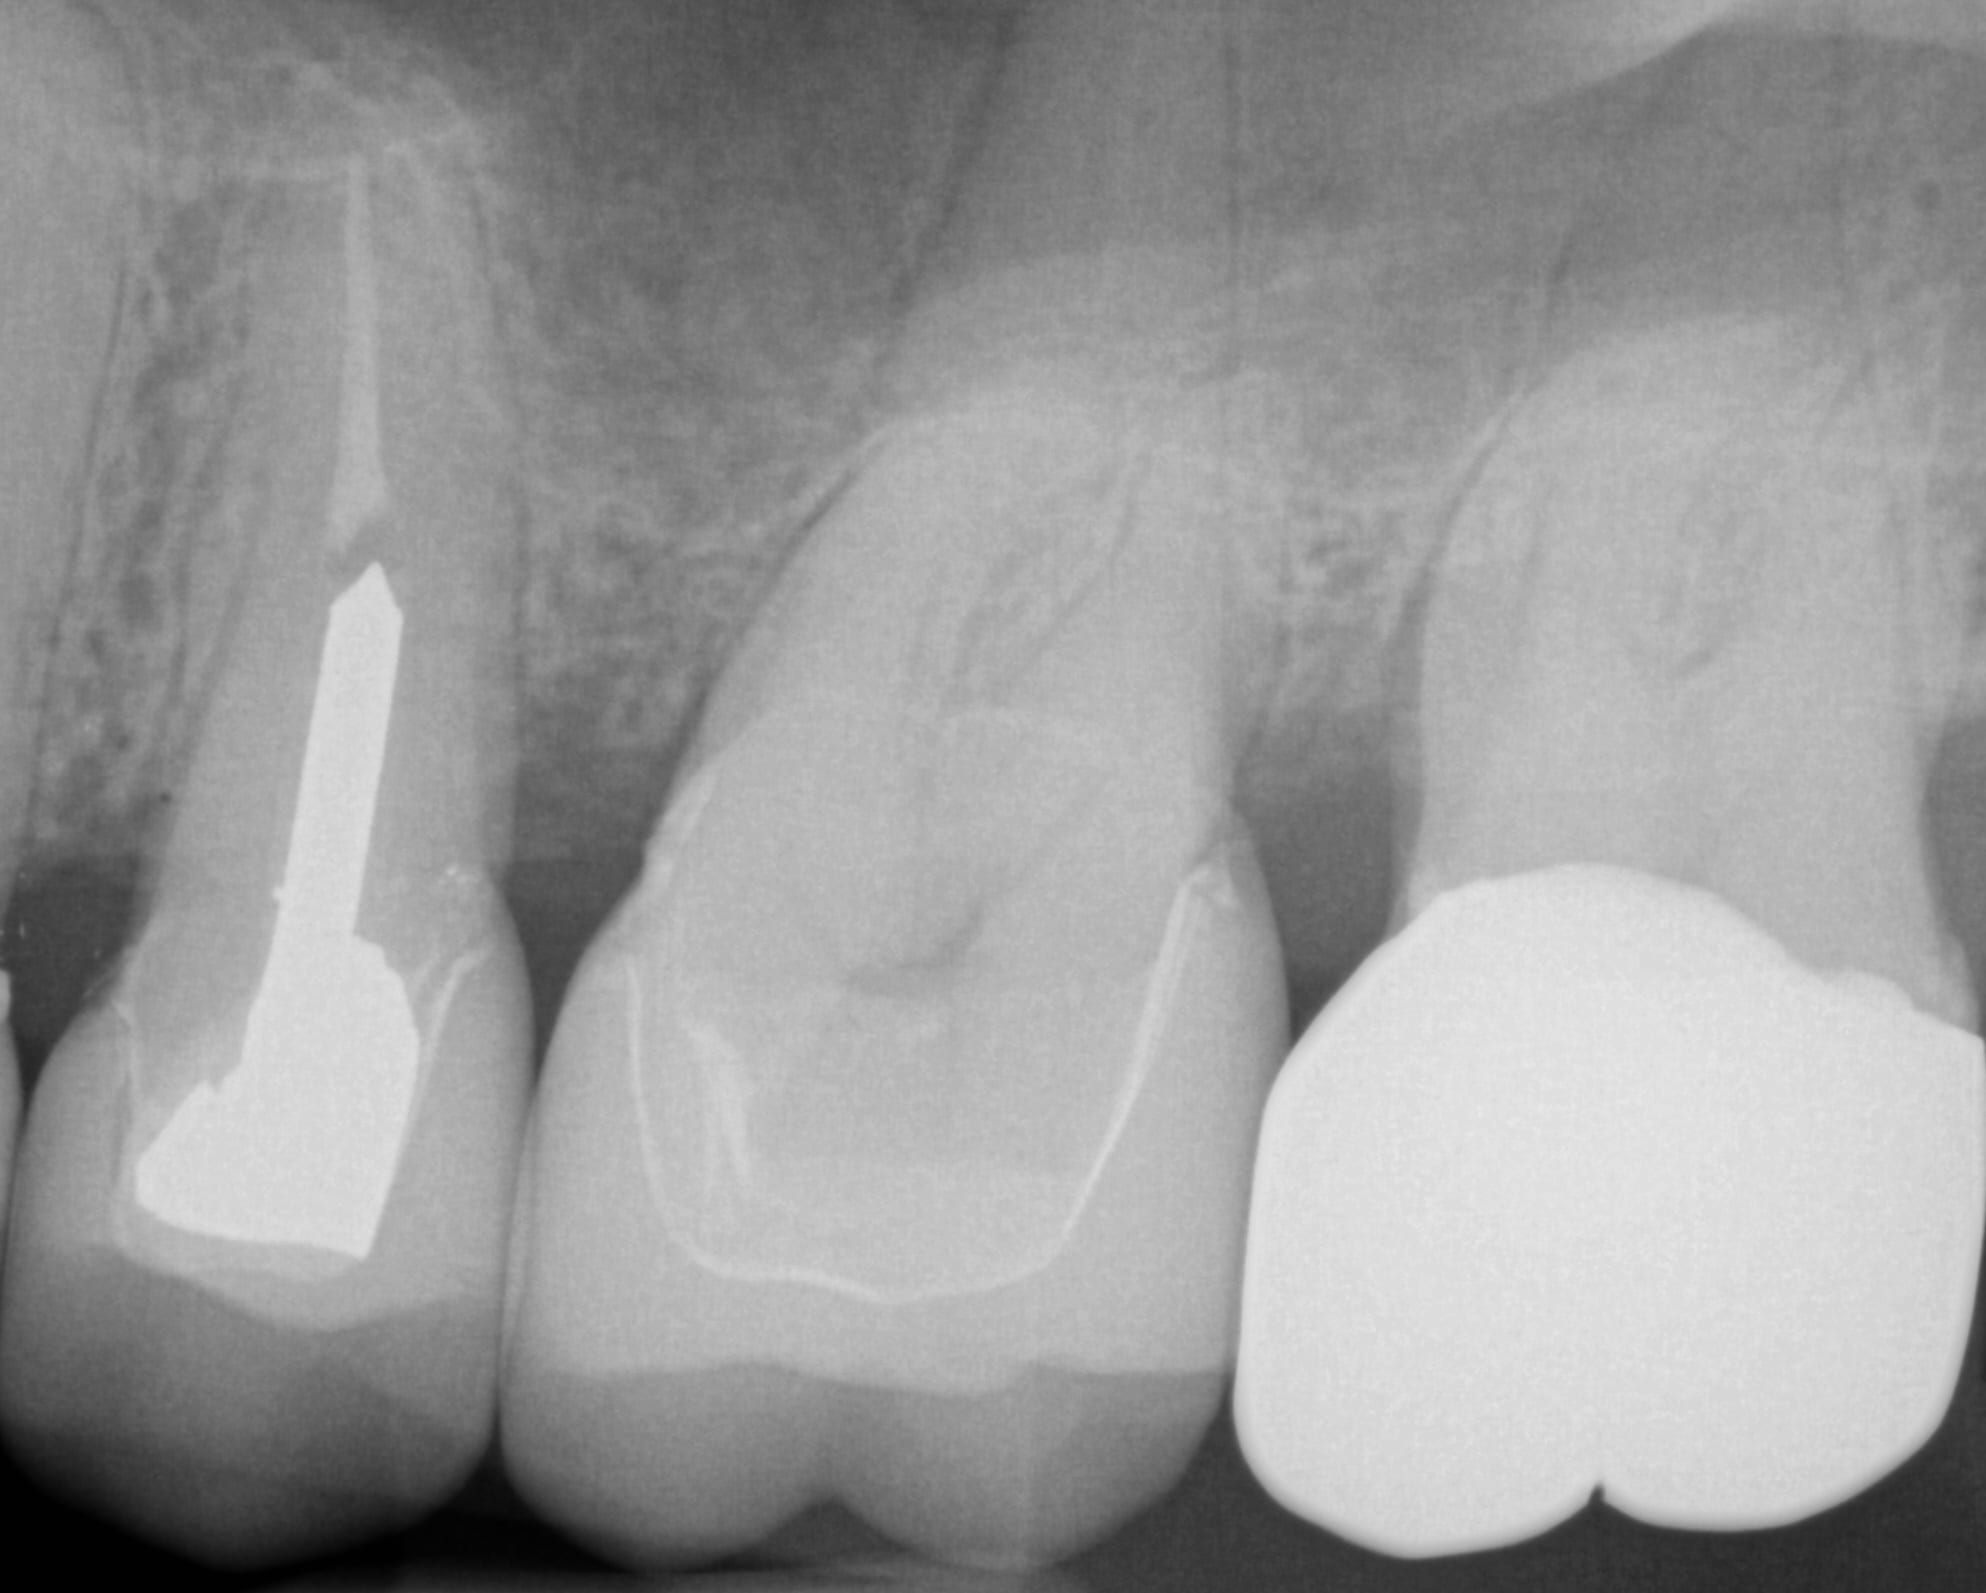

One Month Post Op with Radiographs